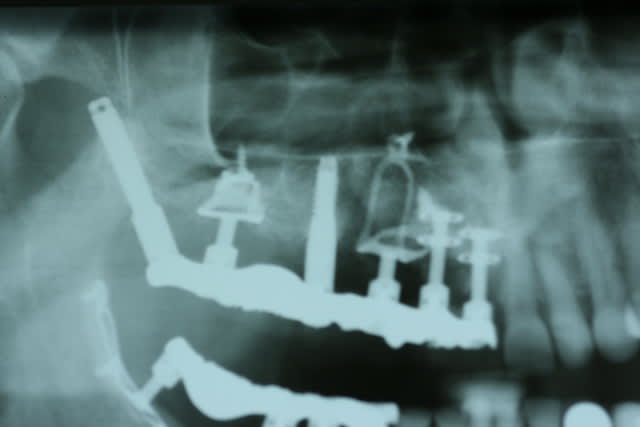

Fabuleuses ces pano avec des diskimplants, ça defit notre mode de pensée implantaire actuel. En tout celui qui a traité ce patient n'était pas un manchot.

En pratique, c'est quoi le problème avec les disk ? On voit pas bien sur la pano periimplantite ? sinon il va y avoir besoin d'encore un peu de titane en secteur 4

et un si grand nombre de disques et 2 implants ptérygoidiens bien posés je ne vois que lui

et je ne vois pas comment ça pourrait bouger : les implants ptérygoidiens sont bien integres

ça aussi c'est fait par le grand Maître, je garderai mon avis pour moi parce que je n'ai pas compris le rationnel pour faire ça à une patiente...